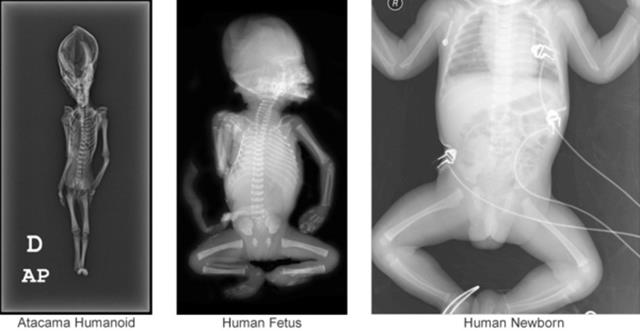

Trước đó, đã từng có một số quan điểm cho rằng đây là một bào thai. Tuy nhiên kết quả phân tích của nhóm nghiên cứu từ trường Đại học Stanford lại cho thấy, không phải như vậy, bởi các mảnh xương của xác ướp này phát triển khá đầy đủ, chứ không phải như của một bào thai. Ngoài ra, so sánh với phim chụp X-quang bào thai cũng cho thấy sự khác biệt rõ ràng về cấu trúc xương.

Quan trọng hơn, xác ướp này có một cái răng phát triển đầy đủ ở khu vực xương hàm (răng hàm), điều này không phù hợp với một bào thai người có kích thước như vậy. Thông thường, phải đến 23 – 33 tháng tuổi thì trẻ mới bắt đầu mọc răng hàm.

Trái: Xác ướp Atacama. Giữa: Bào thai người. Phải: Trẻ em mới sinh. Ảnh: siriusdisclosure.com